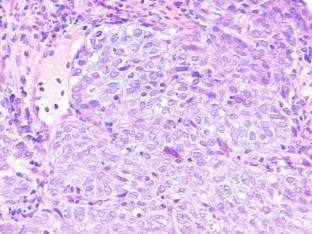

We report a Spanish female who consulted because of fatigue, anorexia, and weight loss. In laboratory data, she presented anemia and markedly elevation of AFP. On CT scan, a gastric mass resulted without hepatic dissemination, and subsequently, gastroduodenoscopy was performed for histological diagnosis. Then, an ulcerated mass was detected and sample was taken, resulting in poorly-differentiated adenocarcinoma of stomach with hepatoid tissue foci, with intense positivity for AFP-immunohistochemical staining. This rare cancer has poor prognosis even with early gastrectomy and chemotherapy.

Fig. 1